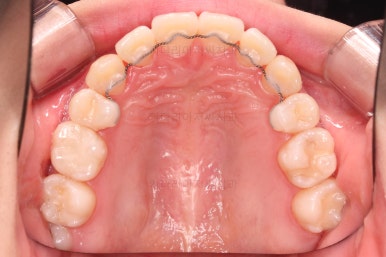

마찬가지로 초진 시 입안의 모습인데요.

전반적으로 약간 삐뚤지만 특히 윗니 앞니가 삐뚤고요.

송곳니는 덧니처럼 튀어나와 보이네요.

그리고 전반적으로 치아가 앞쪽으로 경사되어 있어서 앞니는 뻗친 느낌이 있네요.

가지런하게 하면서 앞니를 뒤로 당겨줘야 여러 가지 문제점들이 개선되기 때문에 발치교정을 했어요.